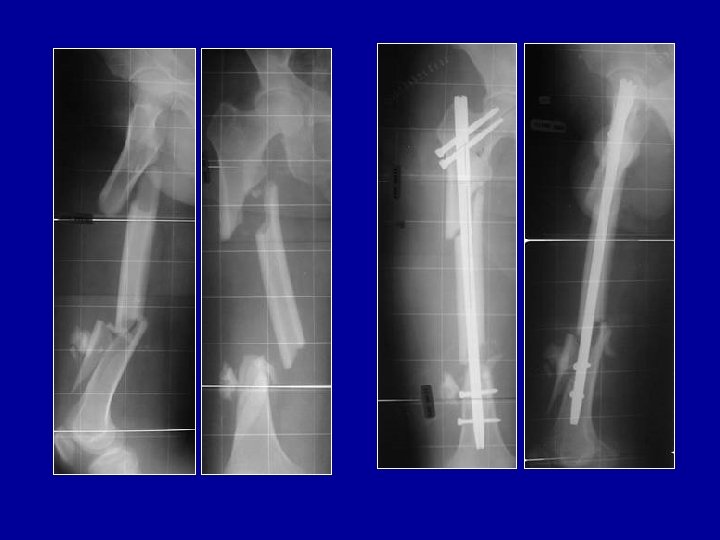

Traitement chirurgical des inégalités des membres Résection-raccourcissement du fémur long et allongement du fémur court avec l’os réséqué puis enclouage des 2 fémurs

Traitement chirurgical des inégalités des membres: Allongement du tibia Allongement progressif par fixateur externe en cadre Allongement par fixateur de Wagner puis greffe et remplacement du fixateur par une plaque

Traitement chirurgical des inégalités des membres Allongement du fémur Allongement par fixateur de Wagner puis greffe et remplacement du fixateur par une plaque